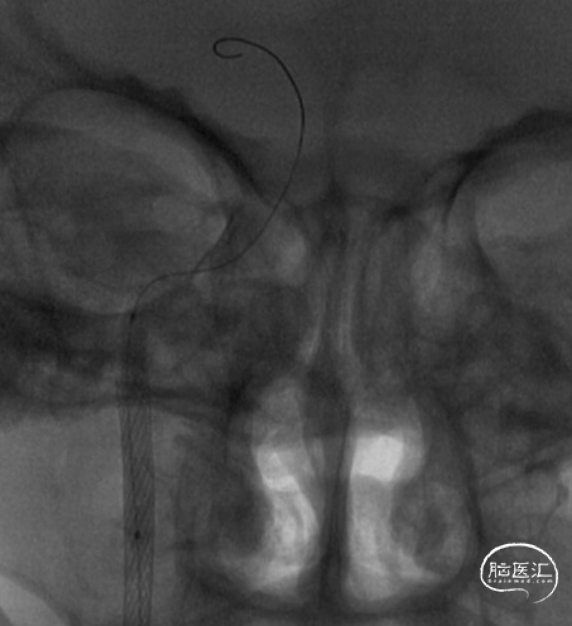

CAT7至C1-C2段多次负压抽吸,抽出大量血栓,C2段以远仍闭塞。

多次抽吸取出的血栓

在清除近端血栓后,微导丝谨慎通过闭塞段

微导丝引导微导管超选至M1段,造影确认真腔

将Syphonet 4*30支架释远端放在M1段,建立远端保护